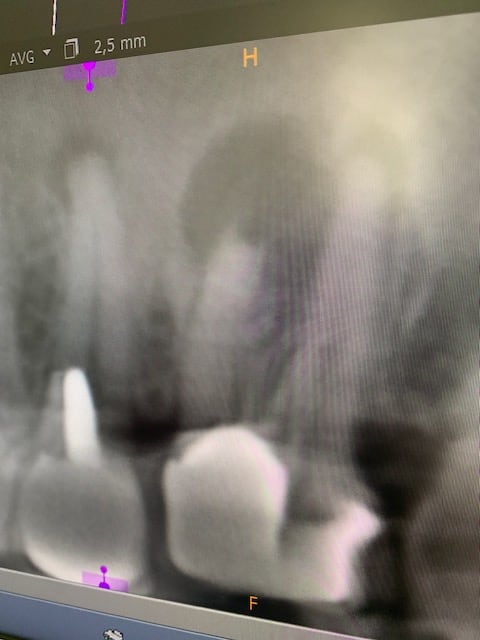

Je te trouve un peu dur dentarue ... heureusement que certains confrères bossent comme des gorets, sinon tu ferais quoi ? Ton cas 25 / 26, c'est 5 minutes pour déposer la 25, 20 minutes au max pour traiter la 25, et 5 minutes pour gicler la 26. Heureusement qu'il a pondu cette bouse le confrère, ça t'evite de faire une endo conventionnée, et poser au mieux 2 zi rac0 ;)

Souricette a fait un taf de ouf et je l’en félicite.

Elle a posé un bridge de 13 à 17 avec molaires en acier pour respecter le c2s. La cotation n’existe pas, mais c’est pas le sujet. Ah, on me dit que si, finalement c’est le sujet, ces putains de molaires en acier ! Que dire, je reste coi…

La patiente a mal, les endos pêchent peut être, chose qu’elle reconnait sans souci, la main sur le portefeuille. Quelle générosité !

Ses radios sont inattaquables, avant, en cours, après, tout est parfaitement documenté, qui pourrait douter ? QUI ?